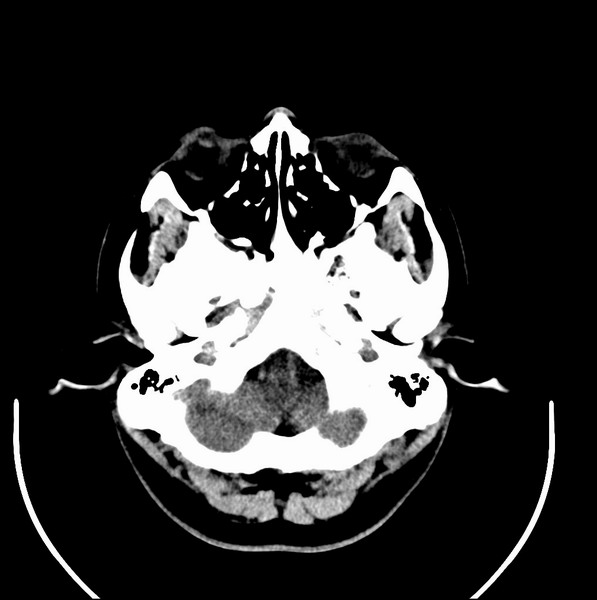

扫描示鼻咽腔不对称,中度狭窄,右侧咽隐窝消失,局部软组织肿块,鼻咽右侧壁增厚形成肿块,突入鼻咽腔,肿块平扫呈等密度,肿块向深部侵润,右侧翼内外肌受侵,右侧咽旁间隙变窄;向后生长,头长肌界线欠清,向后上生长侵犯同侧颈动脉鞘区。双侧海绵窦增宽,内见软组织影与鼻咽部肿块相连。考虑鼻咽癌。鼻咽癌主要是放射治疗,且效果较好;到当地有治疗设备较大医院治疗即可。

典型鼻咽癌侵犯右侧海绵窦(对放疗敏感)

还是先确诊,如果是鼻咽癌,一般行放射治疗;这例患者我首先考虑鼻咽癌